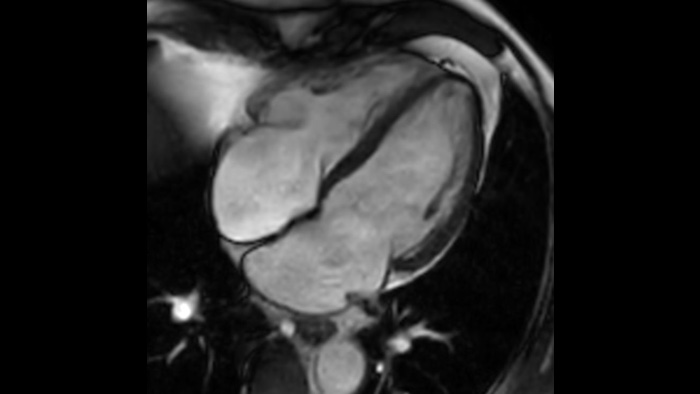

Speed & Comfort Provide up to 40% reduction in breath holds, with virtually equal image quality4.

Diagnostic confidence Expand your imaging capabilities in all clinical areas. See how your peers are benefiting.

There are lots of applications that can improve the workflow. Like Compressed SENSE, VitalEye and VitalScreen. We feel that this system combines both safety and improved workflow.